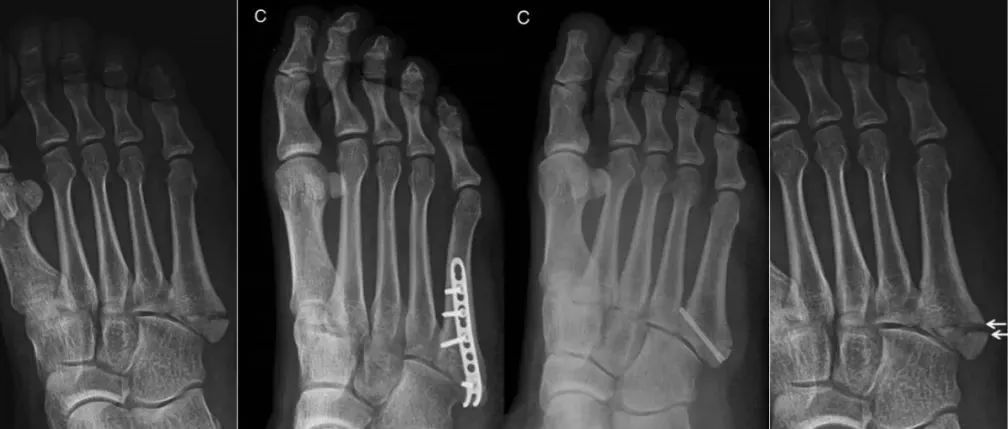

关于「第五跖骨基底部骨折」你都掌握了吗?

第五跖骨基底部骨折治疗不当可导致骨折不愈合或延迟愈合,严重者可出现关节炎,对人们日常生活和工作产生巨大影响。解剖结构第五跖骨是足外侧柱重要组成结构,对于足部负重及维持稳定性上起到重要作用,第四、五跖骨与骰骨构成了跖骰关节。第五跖骨基底部有三条肌腱附着,腓骨短肌腱止于第五跖骨基底部粗隆背外侧;第 3 腓骨肌不如腓骨短肌腱强壮,止于第五跖骨粗隆远侧的骨干;跖腱膜外侧束止于第五跖骨基底粗隆的跖外侧。骨折分型...